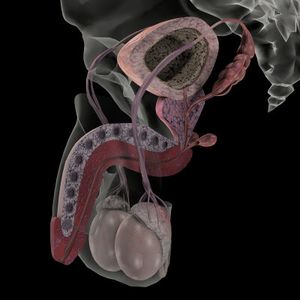

الجهاز التناسلي في الذكر بالإنجليزية Male reproductive system ، هو مجموعة الاعضاء في جسم الذكر التي تلعب دورا في عملية التكاثر الجنسي.

تركيب الجهاز التناسلي الذكري

- كيس الصفن والذي يضم الخصيتين وهي المنتجة للحيوانات المنوية.

- القنوات التناسلية التي تتكون البربخ متصل بوعاء ناقل يصل بدوره إلى الإحليل.

- الغدد التناسلية وتضم كل من الحوصلة المنوية والبروستاتا وغدة كوبر والتي تقوم معا بتكوين بقية مكونات السائل المنوي أو تقوم بوظائف مساعدة.

- الأعضاء التناسلية الخارجية المساعدة، متمثلة بالقضيب والتي تنحصر مهمتها في إيصال الحيوانات المنوية إلى الرحم الإنثوي عن طريق الإيلاج.

يتكون الجهاز التناسلي في الذكر من خصيتين يحاط كل منهما بكيس الصفن الذي يتدلى خارج تجويف البطن , ويخرج من كل خصية قنوات البربخ وكذلك الوعاء الناقل الذي يؤدي إلى الحوصلة المنوية التي يختزن بها الحيوانات المنوية . كما توجد غدد ملحقة بالجهاز التناسلي حتى مجرى البول

تتركب الخصية من عدد كبير من الأنيبيبات الدقيقة الملتوية , كل أنبوبة منها مبطنة من الداخل بخلايا نشطة تقوم بالإنقسام وتكون الأمشاج الذكرية "الحيوانات المنوية" ويوجد بين هذه الأنـيـبـيـبات خلايا بينية تفرز هرمونات الذكورة. وتغلف كلّ خصية محفظة ليفية تسمى الغلالة البيضاء، تتكثف في الخلف لتشكّل المنصف الخصوي الذي يبعث إلى داخل الخصية حجباً ليفية تقسمها إلى نحو 250 فصيصاً، يتألف كلّ فصيص من أنبوب إلى أربعة أنابيب منوية طول كلّ منها نحو 60سم شديدة التعرج، تتجه هذه الأنابيب نحو المنصّف الخصوي حيث يتفاغر بعضها ببعض لتشكّل الشبكة الخصوية التي تصدر عنها الأنابيب الصادرة من الخصية التي تصب في رأس البربخ. يملأ المسافة بين الأنابيب الخصوية نسيج ضام يحوي خلايا لايديغ Leidig المفرزة للتستوستيرون testosterone. أما الأنبوب المنوي فيتألف من غشاء قاعدي تتوضع فوقه خلايا سرتولي Sertoli والخلايا المولدة للنطف spermatogonium. تنشأ الخصية في الحياة الجنينية أسفل الكلية، ثم تهجر مكانها نحو الصفن حيث تبلغه في الشهر السابع من الحمل عادة، وتجر كل خصية معها في أثناء نزولها الأوعية الدموية واللمفاوية والأعصاب الخاصة بها عبر القناة الأربية، وقد تبقى إحدى الخصيتين أو كلاهما فوق القناة الأربية بعد الولادة، وهو ما يسمى اختفاء الخصية cryptorchidism.

يحيط البربخ بالخصية من أحد جانبيها وهو على شكل أنبوب رفيع ملتف على هيئة كتلة ويتصل بنهايته بقناة عضلية هي الوعاء الناقل , ويوجد حول كلا الوعائين الناقلين قبل إلتحامهما بمجرى البول حويصلتين منويتين . يلتحم الوعاء الناقل في تجويف البطن بالقناة البولية أثناء خروجها من المثانة ويمتد المجرى البولي التناسلي خلال القضيب. يرتبط رأس البربخ بالخصية بوساطة الأنابيب الصادرة عنها كما يرتبط بها بمحاذاة ذيله برباط ضام.

يتألف البربخ من أنبوب ملتو كالوشيعة طوله 6-10 أمتار يحيط به نسيج ضام وأوعية دموية، ويتصل البربخ حذاء ذنبه بالأسهر.

الحويصل المنوي

يتوضع خلف الموثة وأعلاها تحت قاعدة المثانة أمام المستقيم، طوله 6سم يتحد مع نهاية الأسهر المجاور لـه من الأنسي ليؤلف القناة الدافقة ejaculatory duct. يحوي كلّ حويصل حجيرات صغيرة متصلة مغطاة ببشرة مفرزة لمواد عديدة أهمها الفروكتوز. وهذه المواد تغذي النطف وتساعد في إنضاجها وحمايتها، وتشكل هذه المفرزات نحو نصف كمية السائل المنوي. تنتهي القناة الدافقة تحت المثانة بقليل في الإحليل الموثي urethra prostatic حيث يصب السائل المنوي أثناء الدفق ضمن الإحليل.

الموثة

القضيب

وهو عضو الجماع والتبويل يتألف من الجسمين الكهفيين corporea cavernosa المشكلين من أسطوانتين إسفنجيتين في الظهر والجانبين ومن الجسم الإسفنجي spongiosum corpus في بطن القضيب، يمر فيه الإحليل الذي ينقل البول والسائل المنوي، ويبدأ بتوسع بصلي الشكل في العجان، وينتهي في ذروة القضيب بكتلة مخروطية الشكل تسمى الحشفة glans التي تغطيها القلفة prepuce.